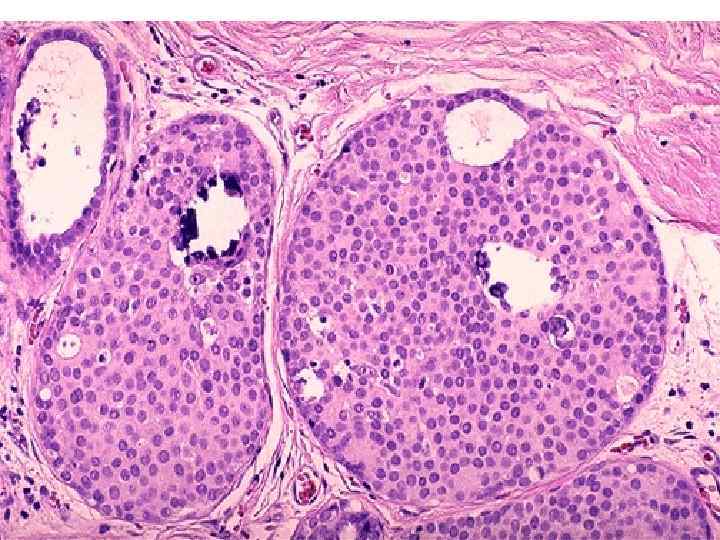

Семинома